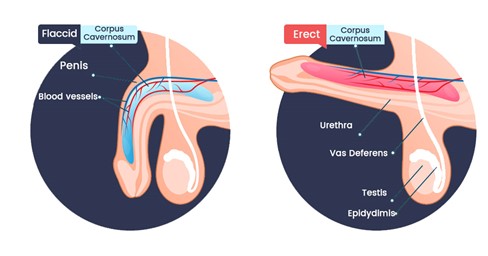

The three systems of an erection

For an erection to happen — and stay — three systems have to work together:

Blood flow in – arteries must open wide enough to flood the penis with blood.

Blood stay – tiny valves in the veins must lock shut, trapping the blood inside.

Signals from the brain – nerves must fire clearly, telling the body “now is the time.”

When these three align, you get a natural, reliable erection.

When even one fails… firmness collapses.

How they break down

Damaged blood vessels: age, stress, high cholesterol or diabetes narrow the arteries, starving the penis of blood.

Weak valves: veins can’t hold the pressure, so the blood escapes within minutes.

Silent nerves: after surgery, illness, or simply time, the nerves go numb, cutting off the vital signal from the brain.